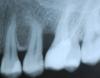

Мартынов Анатолий Опубликовано 17 сентября, 2010 Поделиться Опубликовано 17 сентября, 2010 Пациентка обратилась спустя месяц после "лечения". были боли, дискомфорт. Известно что был мышьяк и пациентка, как сказал ей потом доктор, что-то укусила на врем пломбу, и мышьяк попал на слизистую. вот какая картинка на рентг на втором фото после удаления кусочка кортик кости который болтался. как быть . можно ли восстановить обьем кости? если да, то чем и как. Спасибо Ссылка на комментарий

Voldemar Опубликовано 1 октября, 2010 Поделиться Опубликовано 1 октября, 2010 Выростить интерпроксимальную кость без наличия костных шипов- НЕ ВОЗМОЖНО! У вас нет ни одной костной стенки. Ваше вмешательство приведёт к ещё большей рецессии и углублению кармана. Ссылка на комментарий

Voldemar Опубликовано 3 октября, 2010 Поделиться Опубликовано 3 октября, 2010 Ну при определённых навыках, уложить может и удастся, но материалу нужно трофика, а единственная костная стенка- это дно кармана, корни зубов- не будут трофическими для подсадки, а эпителий- превратит её в себе подобную! Подготовка же реципиентного ложе- приведёт к углублению рецессии! Правило: Интерпроксимальные костные шипы не востанавливаются- незыблемо!!! Ссылка на комментарий

Aldo Rain Опубликовано 3 октября, 2010 Поделиться Опубликовано 3 октября, 2010 сегодня показал эту фотку Николасу Амигони. спросил, что с его точки зрения в данном случае можно предложить?ответ - удаление, подсадка кости, имплантацияудаление только 6-ки? или 5,6? Ссылка на комментарий

Aldo Rain Опубликовано 3 октября, 2010 Поделиться Опубликовано 3 октября, 2010 а что подразумевалось под bone grafting? имплантат и мембрана гортекс или котсный блок до имплантации?моя маленькая имха - что тут надо удалять 5,6, далее сделать синуслифт и одновременно поставить блок по высоте, потом имплантация. Много телодвижений конечно, но костная пластика при включенном дефекте трудновыполнима,еще под сомнением приживление графта к дистальной стенке 5 зуба. Ссылка на комментарий